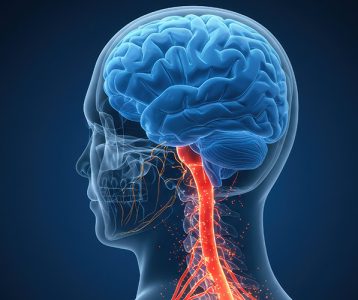

- Probióticos, prebióticos e saúde mental